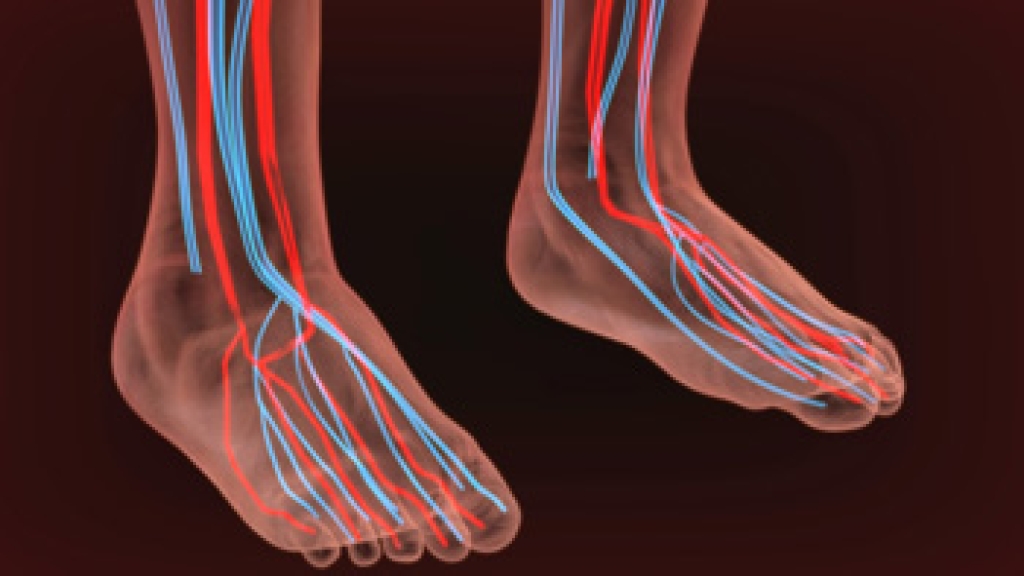

Neuropathy is a condition that leads to damage to the nerves in the body. Peripheral neuropathy, or neuropathy that affects your peripheral nervous system, usually occurs in the feet. Neuropathy can be triggered by a number of different causes. Such causes include diabetes, infections, cancers, disorders, and toxic substances.

Those with diabetes are at serious risk due to being unable to feel an ulcer on their feet. Diabetics usually also suffer from poor blood circulation. This can lead to the wound not healing, infections occurring, and the limb may have to be amputated.

To treat neuropathy in the foot, podiatrists will first diagnose the cause of the neuropathy. Figuring out the underlying cause of the neuropathy will allow the podiatrist to prescribe the best treatment, whether it be caused by diabetes, toxic substance exposure, infection, etc. If the nerve has not died, then it’s possible that sensation may be able to return to the foot.

Pain medication may be issued for pain. Electrical nerve stimulation can be used to stimulate nerves. If the neuropathy is caused from pressure on the nerves, then surgery may be necessary.